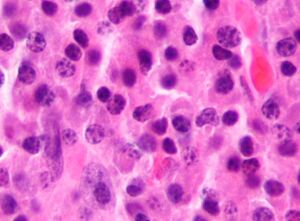

Micrograph of a plasmacytoma. H&E stain | |

Bone marrow aspirate showing the histologic correlate of multiple myeloma under the microscope. H&E stain.